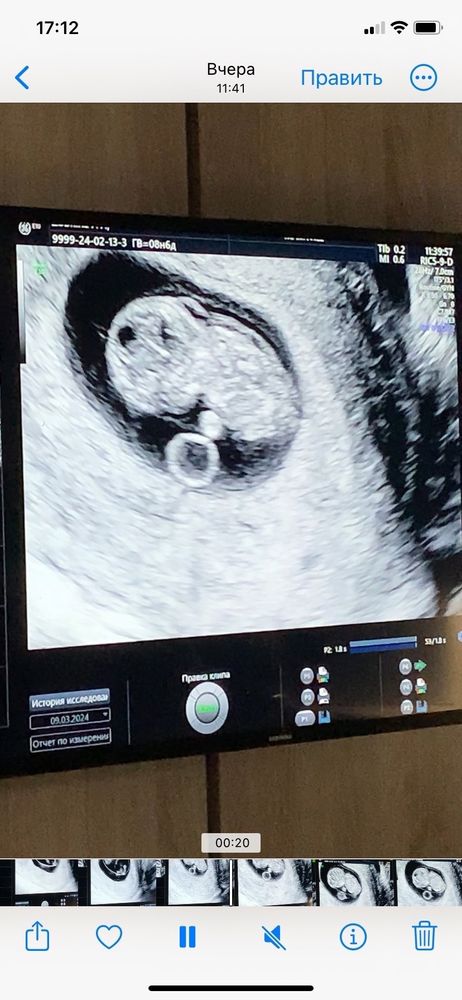

Узи 9 недель

Доброе утро вчера мы с вами здесь общались не думайте о плохом пожалуйста потому что ребёнок все лишь 9 недель молитесь для Бога сложного не чего нету если узист сказала так вас напугала об этом забудьте , могла бы быть еще хуже поэтому не слушайте не кому конечно у знакомая 13 недель когда она сдавала на генетику по результатам сказали у плода ДЦП и на узи сказали спина не ровно !!! Сказали ее делать аборт этот ребёнок родится инвалидом,,,, она не слушала не чего не делала ))) родила мальчика ему сейчас год и 4 месяцев он какой знаете по весу родился 4кг 200 грам так что на Узи нет надо верить они страхует еще понимаете ? 2011 году узнала что беременна как раз первый скрининг и сказала узист у меня замершая беременность тогда для мне была больно ,,, зато у вас ребёнок живёт у вас внутри успокойтесь пожалуйста ❤️❤️❤️❤️я вас понимаю это стоит переживать но это пока рано

Не паникуйте! Спокойно ждите скрининг. Еще рано что-то там искать